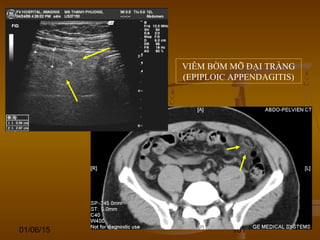

VIÊM BỜM MỠ ĐẠI TRÀNG

(EPIPLOIC APPENDAGITIS)